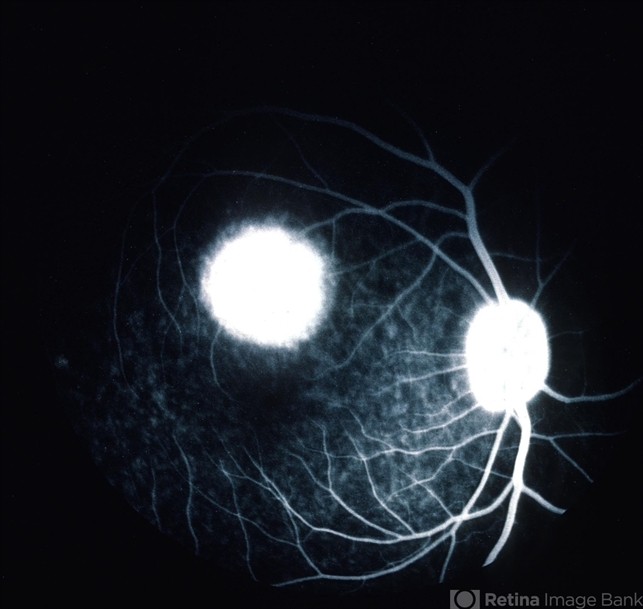

- Angiogram of light toxicity demonstrates hyperfluorescence in the involved area.